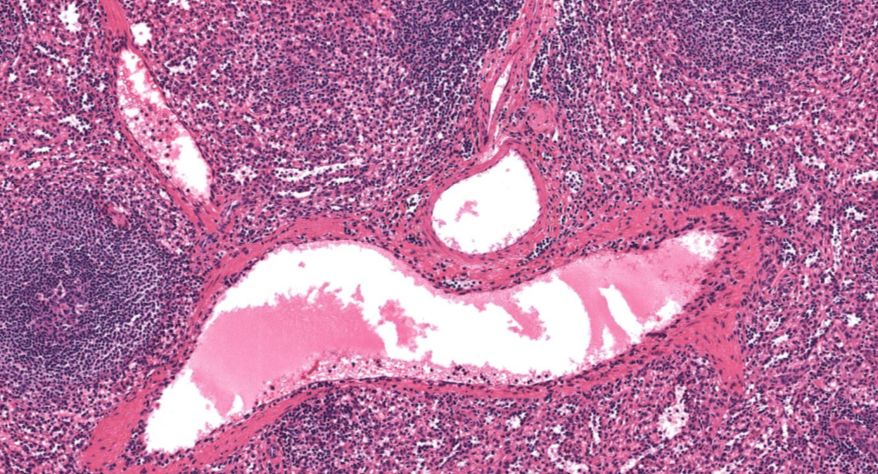

低倍镜:胸腺表面包有薄层结缔组织构成的被膜,结缔组织深入实质,将胸腺分成许多不完整的小叶。每个小叶分为周围的皮质和中央的髓质两部分。皮质中胸腺细胞排列密集,故染色深;髓质中胸腺细胞较少,胸腺上皮细胞多,故染色浅,其中可见染成红色的圆形小体-胸腺小体。高倍镜:胸腺小体大小不等,由几层至十几层扁平的胸腺上皮细胞呈同心圆状排列而成,其外周的细胞较幼稚,细胞核明显;小体中央部分的上皮细胞已退化,细胞核消失,胞质呈均质状,染成红色。

2.被膜

3.皮质